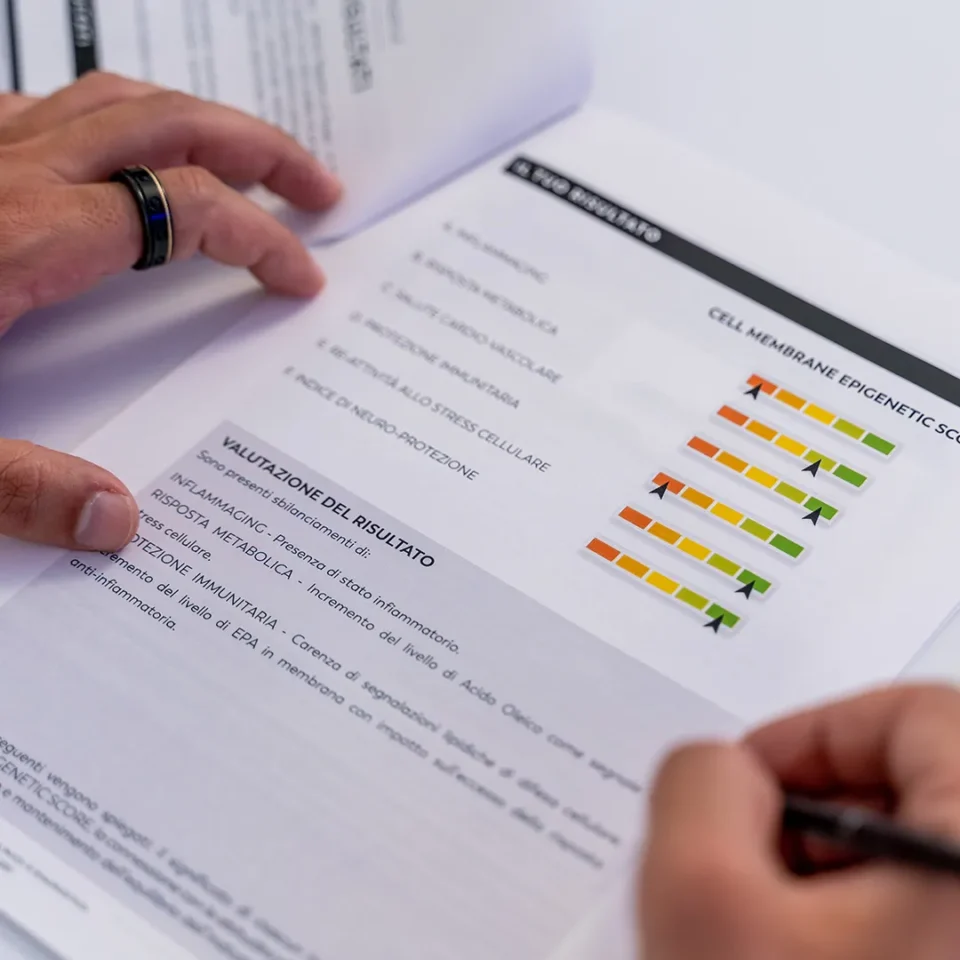

How does your environment affect your genetic makeup? Epigenetic Check-ups consist of a series of analyses that assess how lifestyle impacts the body. We precisely and meticulously evaluate key aspects of your health to optimize your overall well-being and slow down aging processes. This includes assessing epigenetic (biological) age, analyzing intestinal microbiota using advanced DNA sequencing techniques, and mapping sleep quality —a fundamental process that regulates critical biological functions underlying health and well-being.

Assessment of biological age through the evaluation of key longevity biomarkers within the hormonal profile. The results include analysis of four specific markers such as inflammation, estrogen-dominance, skin health, and longevity.